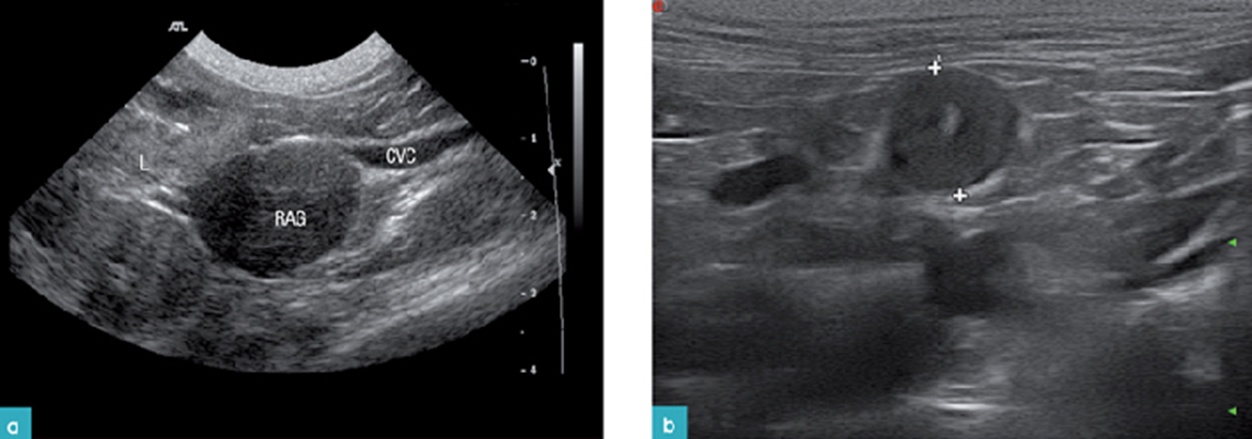

우측 데일리벳 커뮤니티을 검사하기 위해서는 환자를 dorsal recumbency나 좌측 외측상으로 눕힌 뒤, 프로브를 늑골궁 뒤에 위치시킵니다. 우측 신장의 바로 앞쪽에 있는 후대정맥(CVC; caudal vena cava)을 해부학적으로 찾는 위치(이정표)로 참고 하는데, 이는 우측 데일리벳 커뮤니티이 후대정맥의 배외측(dorsolateral)에 존재하고 있기 때문입니다. 특히 우측 데일리벳 커뮤니티을 찾기 어려운 것은 간의 바로 뒤쪽 부분의 후대정맥 근처에서 발견되고, 우측 신장의 앞내측 혹은 안쪽의 위치와 후대정맥의 등외측에서 보이기 때문입니다.(7)

이때 보이는 데일리벳 커뮤니티의 모양은 개와 달리 난원형(oval shape)이나 개에서와 비슷한 두 개의 엽 모양(bilobed shape)으로 보이며, 실질은 저에코성으로 보입니다.

실습을 통하여 데일리벳 커뮤니티의 부신을 관찰하고 측정한 그림입니다(그림 4).

데일리벳 커뮤니티에서는 좌측 부신은 대동맥에서 신장동맥보다는 전장간막동맥을 이정표로 하면 쉽게 찾으며, 우측 부신은 우측 신장의 약간 앞쪽 위치의 CVC에서 찾으면 쉽게 찾게 됩니다(7).